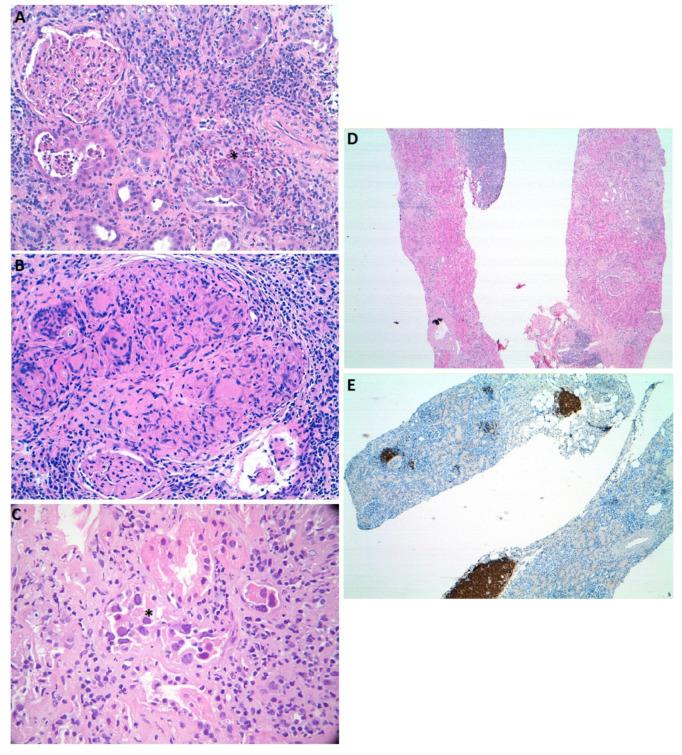

Acute kidney injury in patients who suffer a malignancy is a common complication. Due to its high prevalence and effective treatment, one of the most frequent causes that both oncologists and nephrologists must be aware of is acute tubulointerstitial nephritis (ATIN). ATIN is an immunomediated condition and the hallmark of the disease, with the presence of a tubulointerstitial inflammatory infiltrate in the renal parenchyma. This infiltrate is composed mainly of T lymphocytes that can be accompanied by macrophages, neutrophils, or eosinophils among other cells. One of the major causes is drug-related ATIN, and some antineoplastic treatments have been related to this condition. Worthy of note are the novel immunotherapy treatments aimed at enhancing natural immunity in order to defeat cancer cells. In the context of the immunosuppression status affecting ATIN patients, some pathogen antigens can trigger the development of the disease. Finally, hematological malignancies can also manifest in the kidney leading to ATIN, even at the debut of the disease. In this review, we aim to comprehensively examine differential diagnosis of ATIN in the setting of a neoplastic patient.

患有恶性肿瘤的患者发生急性肾损伤是一种常见的并发症。由于其高患病率和有效的治疗方法,肿瘤科医生和肾病科医生都必须了解的最常见原因之一是急性肾小管间质性肾炎(ATIN)。ATIN 是一种免疫介导的疾病,其特征是肾实质中存在肾小管间质性炎症浸润。这种浸润主要由 T 淋巴细胞组成,其中可伴有巨噬细胞、中性粒细胞或嗜酸性粒细胞等其他细胞。主要原因之一是与药物相关的 ATIN,一些抗肿瘤治疗与这种情况有关。值得注意的是,旨在增强天然免疫以战胜癌细胞的新型免疫疗法。在影响 ATIN 患者的免疫抑制状态的背景下,一些病原体抗原可引发疾病的发展。最后,血液系统恶性肿瘤也可在肾脏中表现出来,导致 ATIN,甚至在疾病的首发时。在这篇综述中,我们旨在全面检查肿瘤患者中 ATIN 的鉴别诊断。